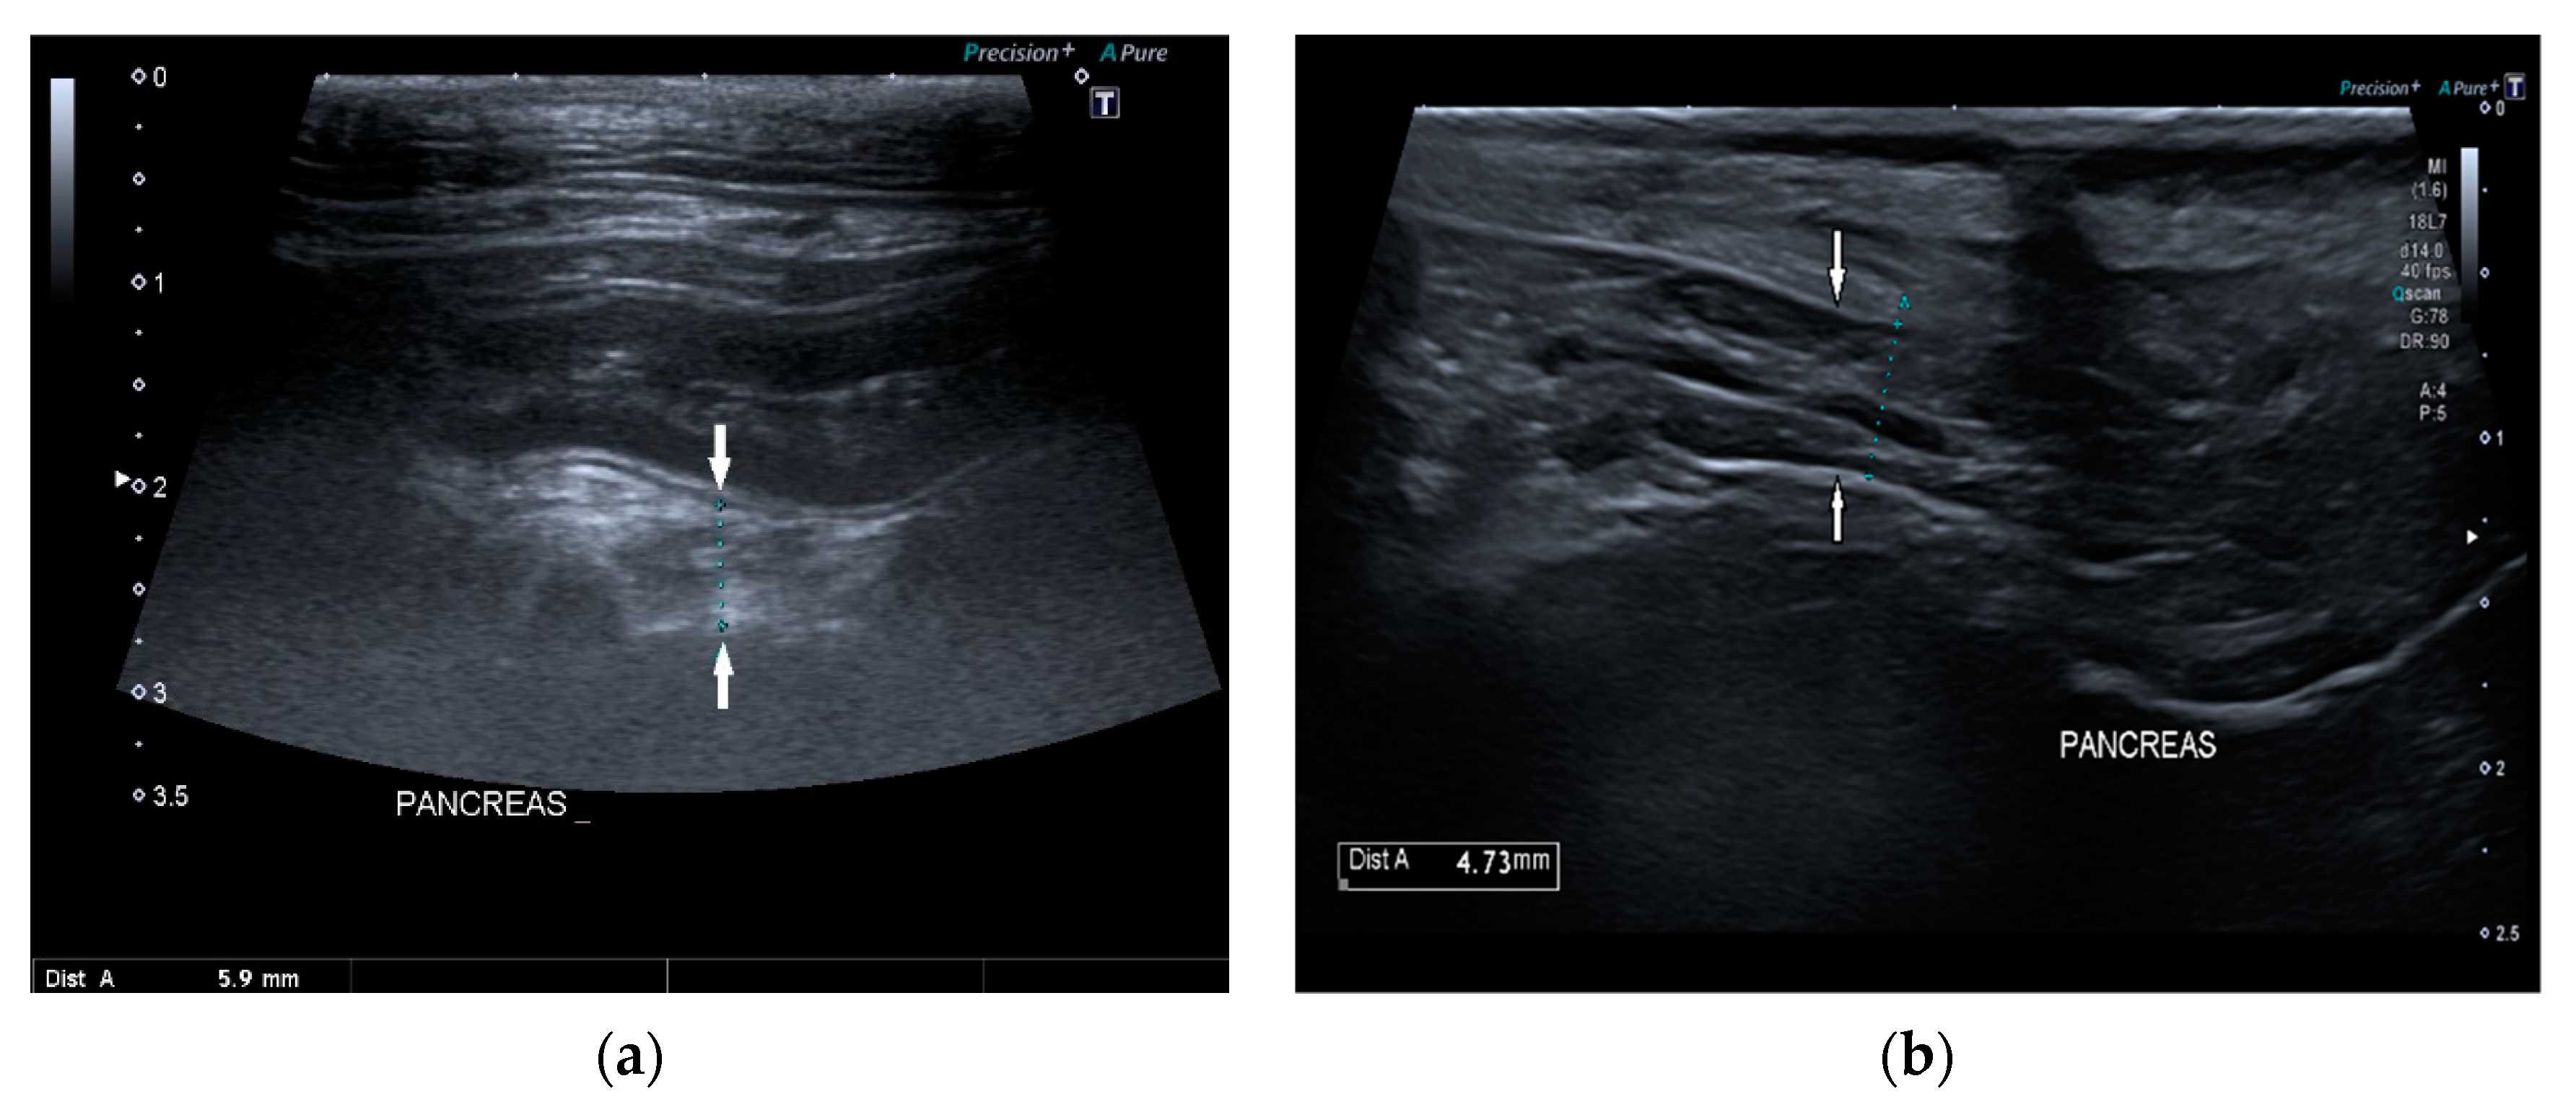

Pancreatic size was determined using calipers on a video frame or a still image. As described in the previous study, given that the pancreas has a triangular shape, it was considered a good compromise to measure its thickness perpendicular to the long axis [17]. Due to the low identification rate of the left pancreas in dogs, the pancreatic thickness was evaluated by measuring the right lobe located ventromedial to the right kidney and medial to the descending duodenum (Figure 1) [17].

Figure 1.

Ultrasound images (a) and (b) of the right pancreatic limb (between white arrows) with caliper measurement.